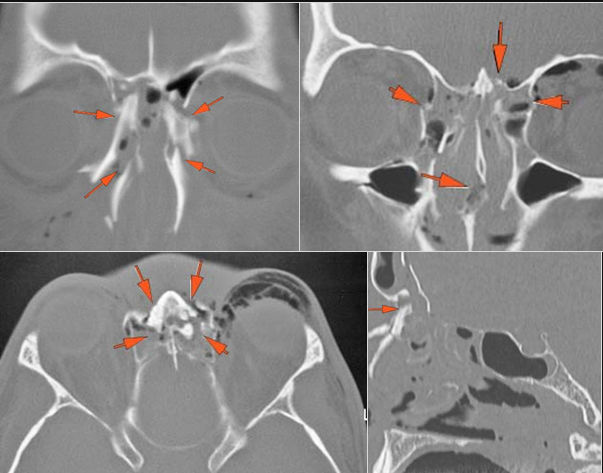

The medial, lateral and posterior maxillary walls are fractured. [Yes/No]

The infraorbital rims and orbital process of the zygoma and/or frontozygomatic suture are fractured. [Yes/No]

The alveolar ridge, premaxilla, and/or the palatine process of the maxillary bones on either side are fractured. [Yes/No]

The hard palate is fractured. [Yes/No]

The pterygoid processes of the sphenoid bone are fractured. [Yes/No]

Fronto-Naso-Ethmoidal Complex

The mesial naso-orbito-ethmoid complex is fractured. Specifically, there is bony injury of the nasal bones or the frontal process of the maxilla and the medial walls of the orbit are abnormal. [Yes/No]

There is injury of the ethmoid complex. Specifically, the ethmoid roof, olfactory fossa and the cribriform plate are fractured and/or significantly dehiscent. [Yes/No]

The frontal bone and frontal sinus inner and outer tables are fractured. [Yes/No]

The the zygomatic arch, frontozygomatic suture or infraorbital rim are fractured. [Yes/No]

The lateral wall of the orbit is fractured. [Yes/No]

There is fracture of the greater or lesser wing of the sphenoid bone, optic strut and canal, or basisphenoid, in the region of the orbital apex. [Yes/No]